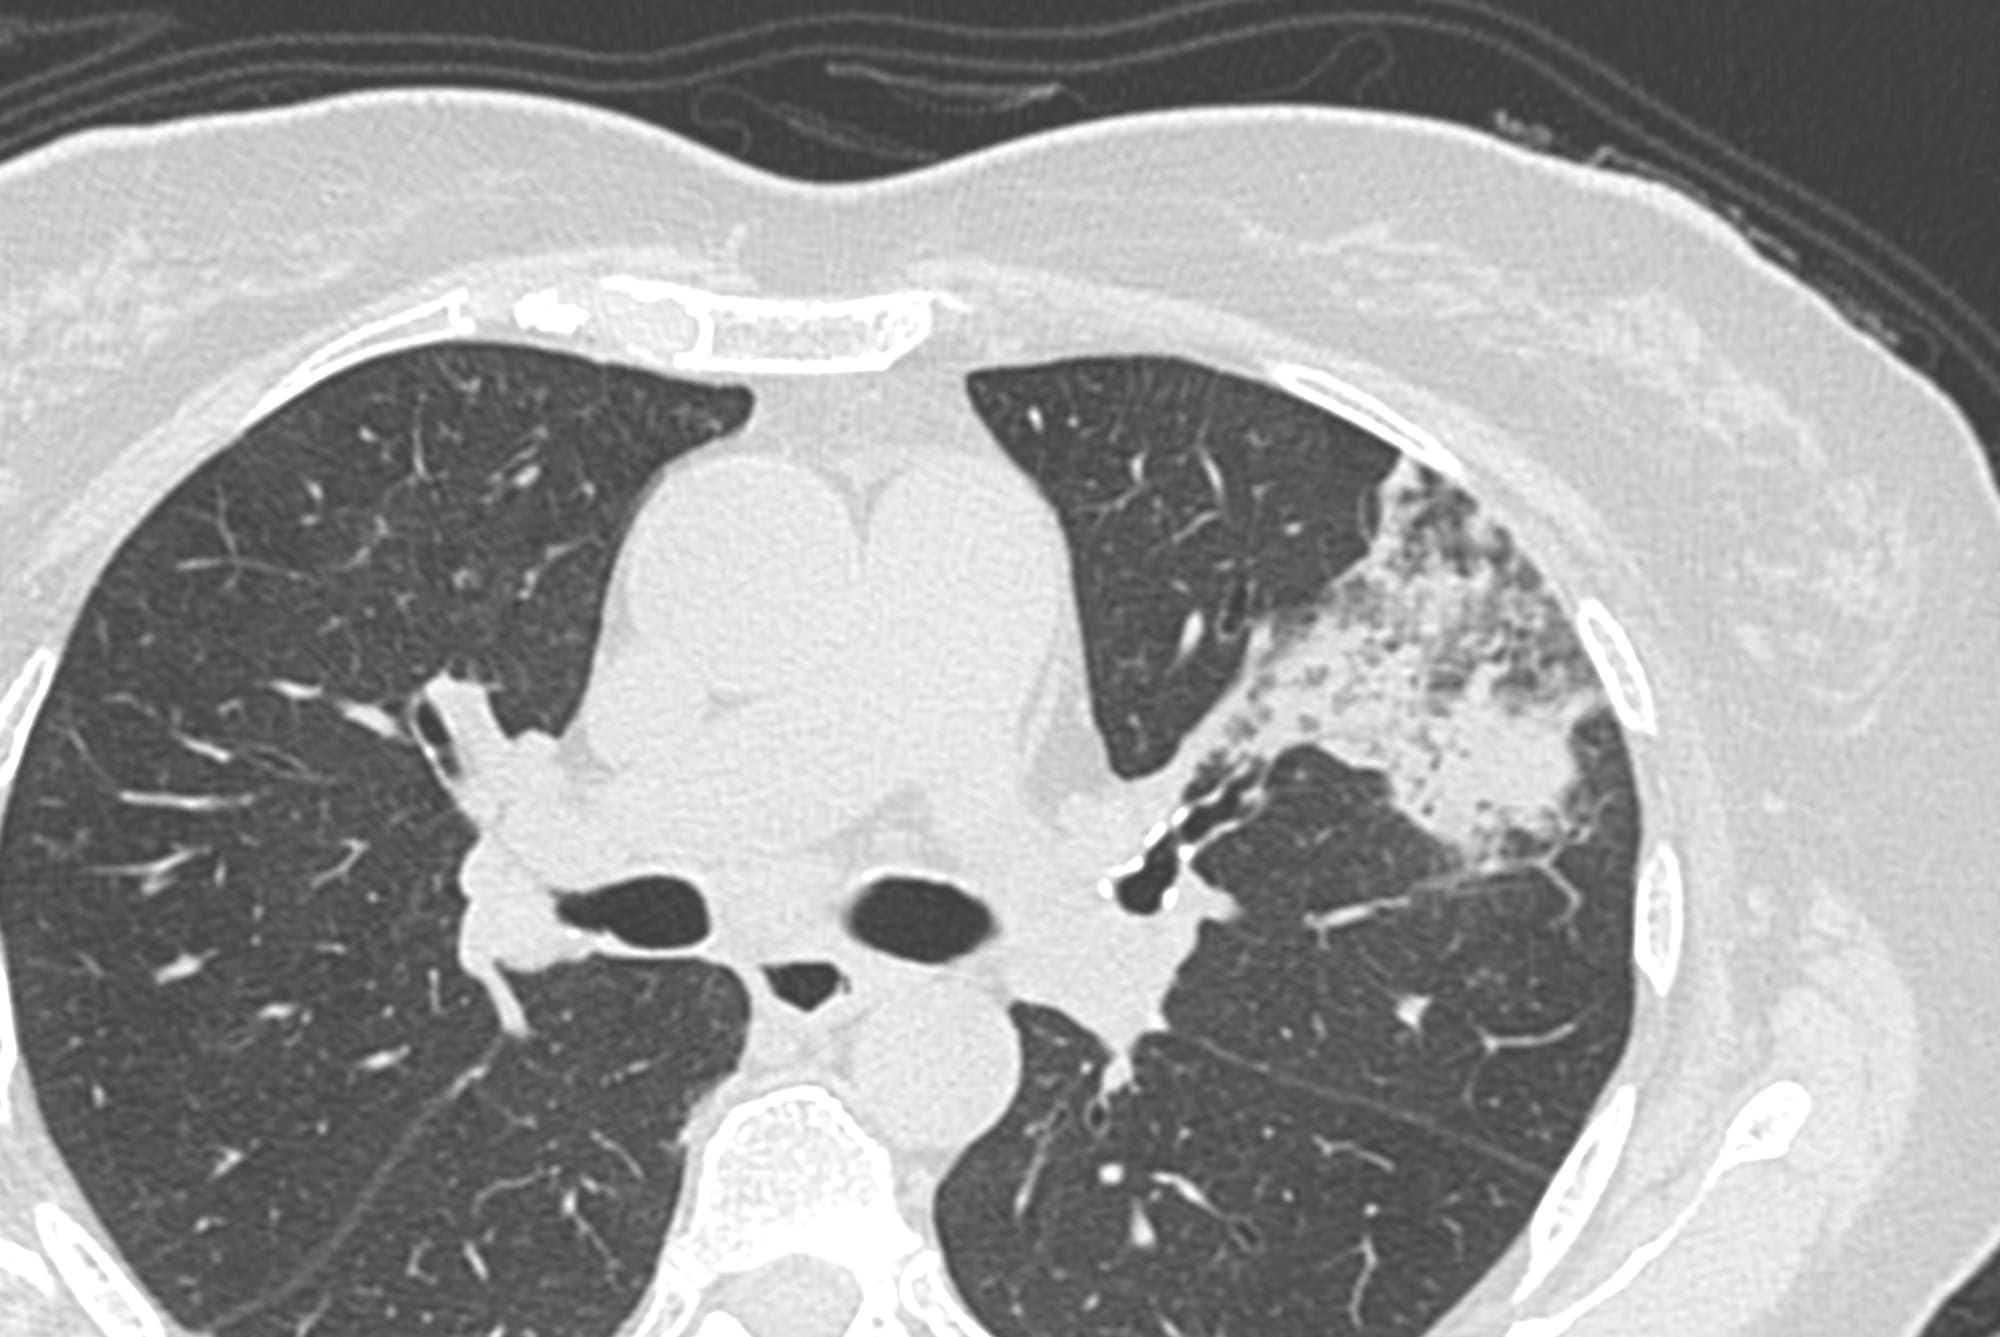

Current Case:

59-years old with fever and non-resolving consolidation

What would be your approach?

The video below describes the case and the reason for performing a biopsy parallel to the vessels and not perpendicular